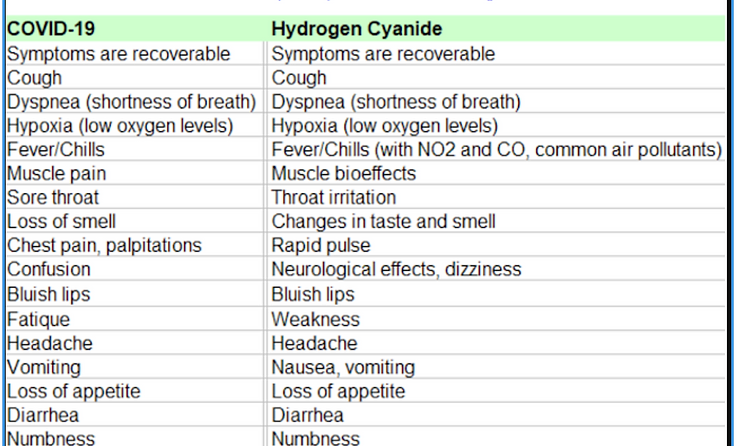

A recent Harvard study finds that those vulnerable to the symptoms of the so-called “virus” are generated by long-term chemical poisoning from air pollution. A small increase in long-term exposure to PM2.5 leads to a large increase in the symptoms and death rate claimed to be caused by the phantom virus, COVID-19 … 1 μg/m3 in PM2.5 of hydrogen cyanide air pollution poisoning is associated with an 8% increase in the COVID-19 death rate. Once again, the increase in the COVID-19 death rate is due to chemical poisoning from air pollution and NOT from an invisible phantom virus. As you can see in the chart below hydrogen cyanide poisoning and its symptoms are identical to those claimed as an infectious virus now known as COVID-19 which has never been scientifically identified, isolated and cultured under Koch’s postulates, validating its existence of so-called virus. [14]